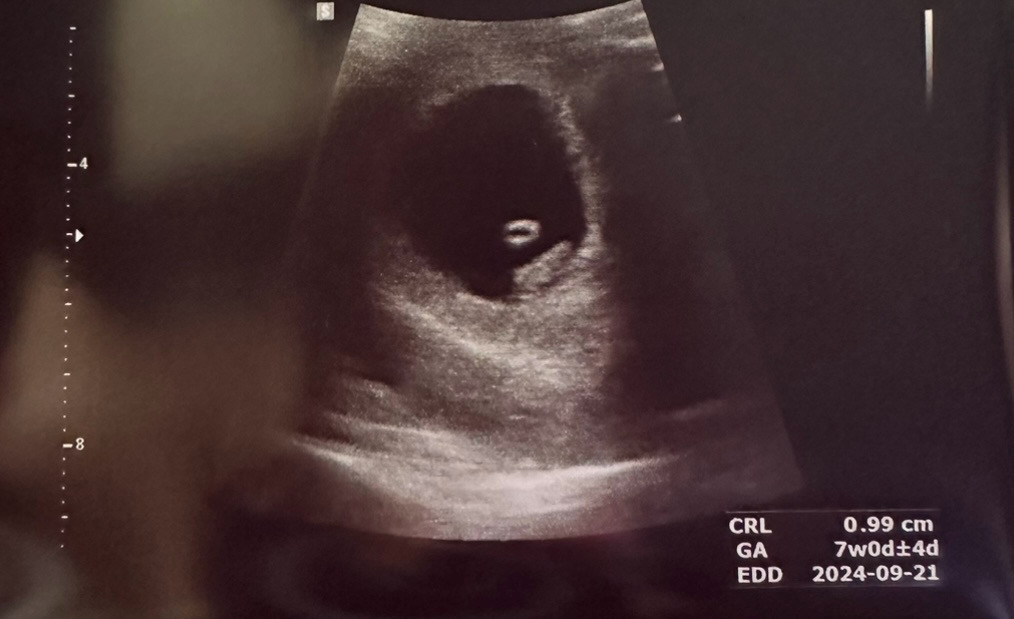

7주차0일 심소듣고 왔어요!

요즘 갈증때문에 너무 힘들었는데 2주 사이에 아기집이 엄청 커졌더라구요ㅋㅋㅋㅋ 너무 신기해요 진짜 그동안 마신 물이 다 여기로 갔나봐요... 심장 뛰는 것도 우렁차서 당분간 마음이 안정될 것 같아요😌